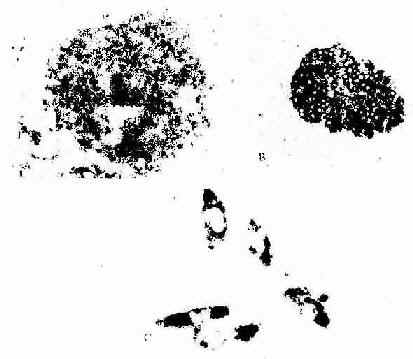

图1-12 原位杂交术光镜像

A 32P标记胰岛素cRNA探针放射自显影显示大鼠胰岛B细胞内胰岛素mRNa

B 地高辛-碱性磷酸酶标记胰岛素cRNA探针显示大鼠胰岛B细胞内胰岛素mRNA

C 地高辛-碱性磷酸酶标记心钠素cRNA探针显色示体外培养的人胎儿脐静脉

内皮细胞内的心钠素mRNA ×850

(第三军医大学蔡文教授供图)